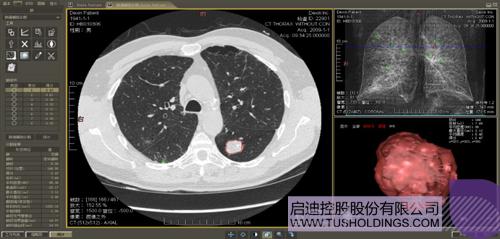

Êý×ַβúÆ··Î°©ÅÌËã»ú¸¨ÖúÕï¶Ï

Ò½ÁÆÓ°ÏñÖÇÄÜÆÊÎöÊÇÖ¸ÔËÓÃÈ˹¤ÖÇÄܼ¼Êõ¡¢ÅÌËã»úÊÓ¾õ¼¼ÊõÒÔ¼°ÅÌË㼸ºÎ¼¼Êõ¶ÔÒ½ÁÆÓ°Ïñ½øÐÐ×Ô¶¯ÆÊÎö  £¬×ÊÖúÒ½Éú¶¨Î»²¡Ö¢¡¢ÆÊÎö¡¢¸ú×Ù²¡Çé  £¬²¢Í¨¹ýÁ¿»¯Êý¾Ý¸¨ÖúÒ½Éú×ö³öÕï¶Ï  £¬Ä¿Ç°ÆäÆì½¢²úÆ·¡°Êý×ַΡ±ÒѾ­ÁýÕÖ¶àÖַβ¿¼²²¡µÄÔçÆÚ¼ì²â¡¢Õï¶Ï¡¢¸ú×Ù¡¢Êõǰ¼Æ»®µÈÍêÕûµÄÒ½ÁÆÁ÷³Ì ¡£ÔÚÁÙ´²Êµ¼ùÖÐ  £¬Áè¼Ý80%µÄÒ½ÁÆÊý¾ÝÀ´×ÔÒ½ÁÆÓ°Ïñ  £¬ÕâЩӰÏñÊý¾Ýͨ³£ÐèҪרҵҽÉú½øÐнâ¶Á  £¬ÊÂÇéµÄÖØ¸´ÐԸߡ¢Ð§ÂÊÆ«µÍ ¡£Èç¹ûÄܹ»ÔËÓÃÖÇÄÜÓ°ÏñÆÊÎö¼¼Êõ  £¬Í¬Ê±½áºÏÁÙ´²ÌåÏÖÒÔ¼°¼ÈÍù²¡Àý½øÐÐÈ«ÃæÆÊÎö  £¬ÄÇô¾Í¿ÉÒÔ´ó·ù¶ÈÌáÉýÓ°ÏñÕï¶ÏЧÂʺÍ׼ȷÐÔ  £¬ÈÃרҵҽÉúµÄÃû¹óʱ¼ä¼¯ÖÐÔÚÅÓ´ó²¡ÇéµÄÕï¶ÏºÍÖÎÁƵȻ·½Ú ¡£

Êý×ַΡª¡ª·Î½á½ÚÊÖÊõ¼Æ»®ÏµÍ³